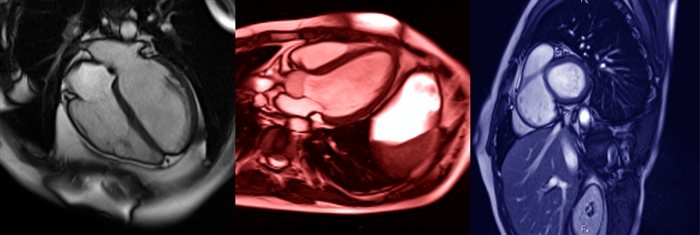

心臓MRI

心臓MRIでわかること

心臓の筋肉の病気である

心筋症(しんきんしょう)の有無や

心臓の動き・形の異常を発見できます。

心臓のポンプ機能の異常である

心不全や不整脈の原因

を詳しく調べるのに役立ちます。

↓実際の心臓MRIの画像。心エコーよりもさらに詳しく心臓をみることができます。